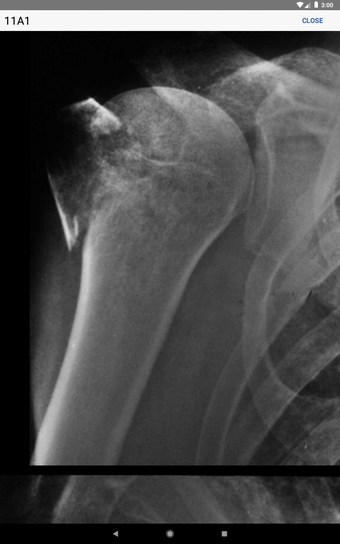

Entre sus características destacan la información sobre investigaciones radiológicas necesarias para clasificar fracturas específicas, así como la identificación de errores comunes en las imágenes. Incluye ilustraciones de fracturas actualizadas y radiografías de alta calidad que se pueden ampliar. Además, los códigos de fractura se pueden guardar en una lista de "Favoritos" para un acceso personalizado, y una nueva función de búsqueda permite acceder rápidamente a cualquier código de fractura, mejorando la eficiencia en la evaluación de resultados de lesiones.